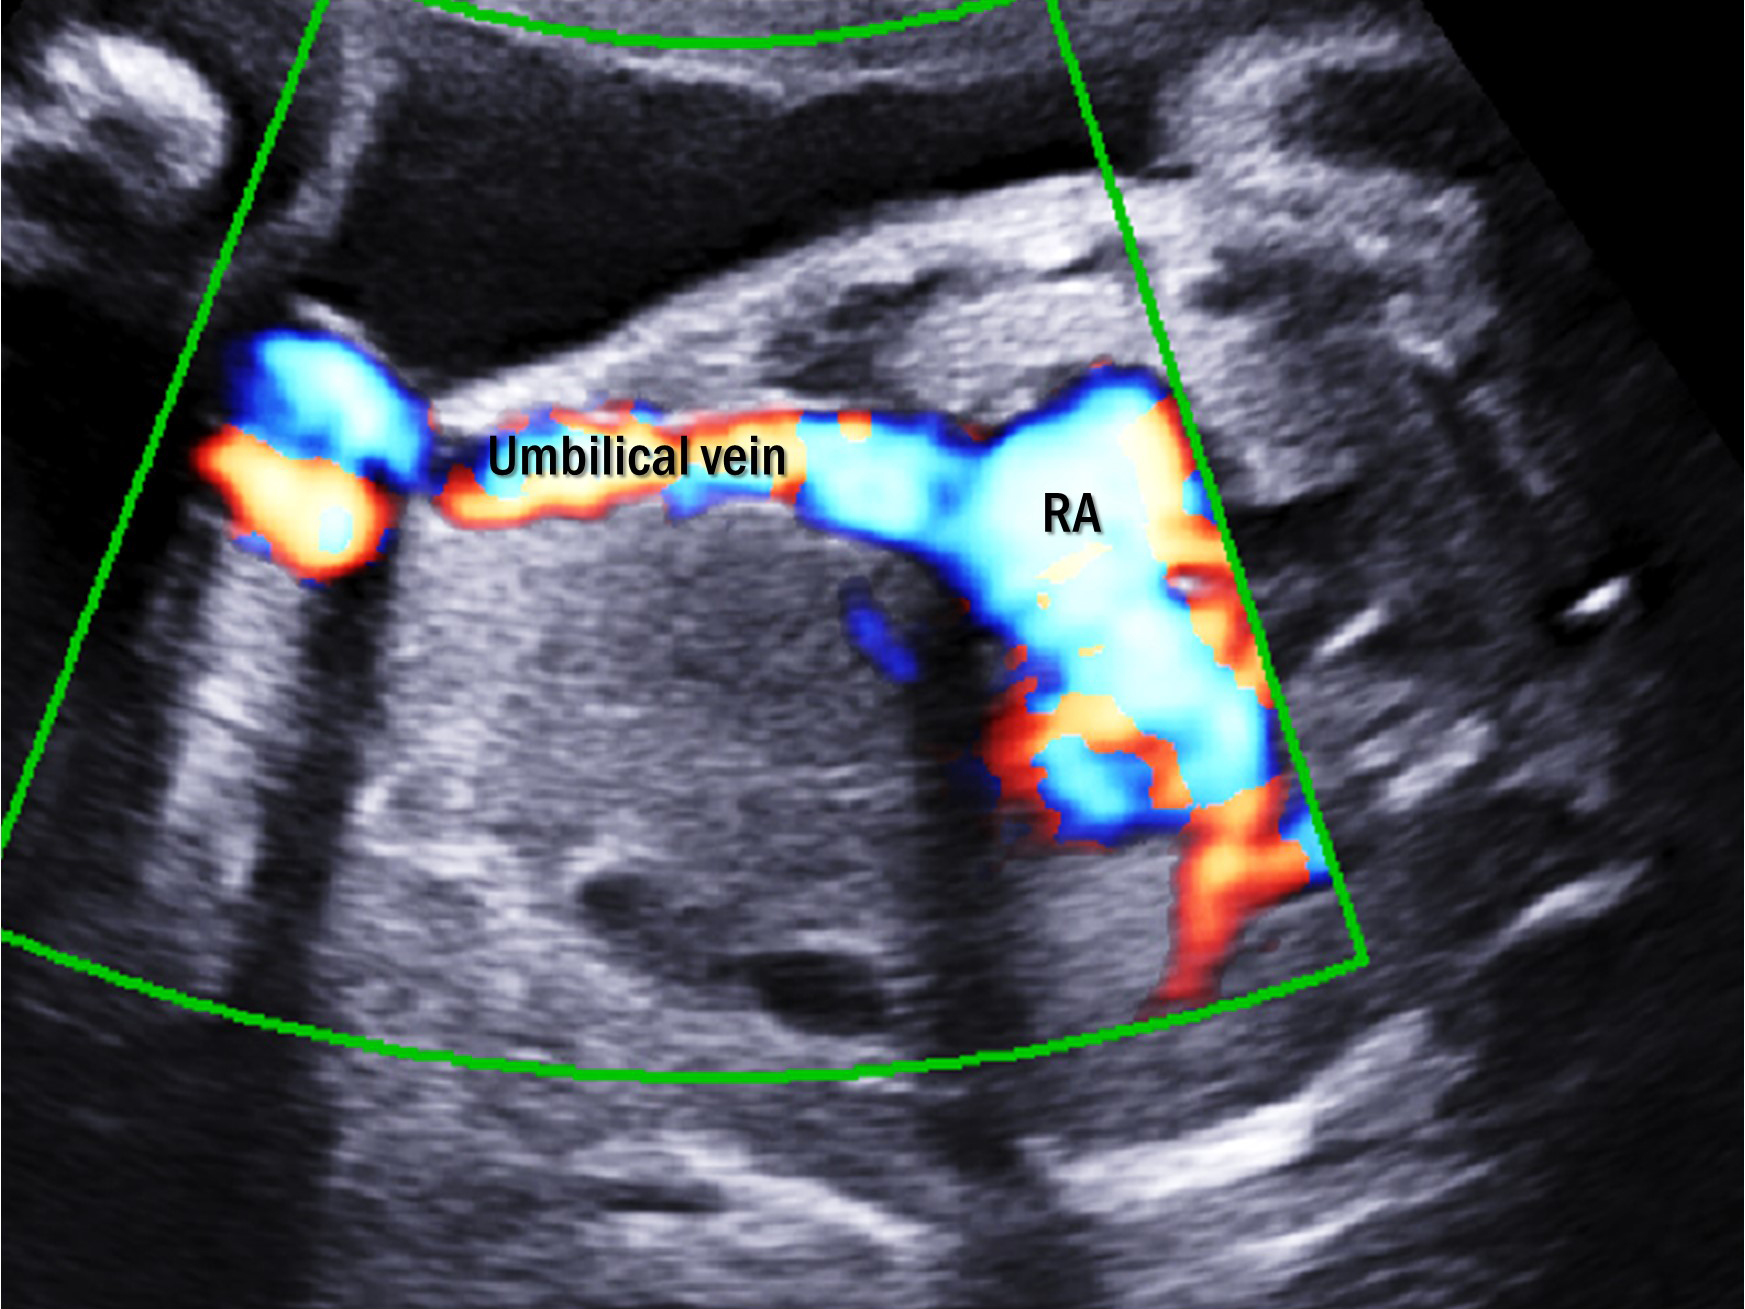

There were eight cases of type I UPSVS. These cases did not show any DV, and the UV was connected to the systemic vein. In six cases (cases 1, 4–8), the UV directly drained into the right atrium (Fig. 2). In two cases (cases 2 and 3), the UV drained into the inferior vena cava (IVC). All but one (7/8, 88%) were associated with other structural abnormalities: two cases with VACTERL association (cases 6 and 8), which included three or more combinations of vertebral defects (V), anal atresia (A), cardiac abnormalities (C), tracheoesophageal fistula (TE), renal abnormalities (R), and limb defect (L). And one case with Cornelia de Lange syndrome (case 3), which shows distinctive facial characteristics and growth delays [8]. The patient with trisomy 18 died at the age of seven months because of respiratory failure due to tracheomalacia (case 5). Cardiomegaly was observed in five fetuses, three of which resolved. The median GA at birth was 38.1 weeks (range, 33.3–39.4) and the median birth weight was 2540 g (range, 1910–2870). Five neonates had birth weights below the 10th percentile, and four of them were below the 3rd percentile.

Fig. 2.Two-dimensional color Doppler image of type I umbilical-portal-systemic venous shunt in case 7. Umbilical vein directly drains into the right atrium without going through the ductus venosus. RA, right atrium.